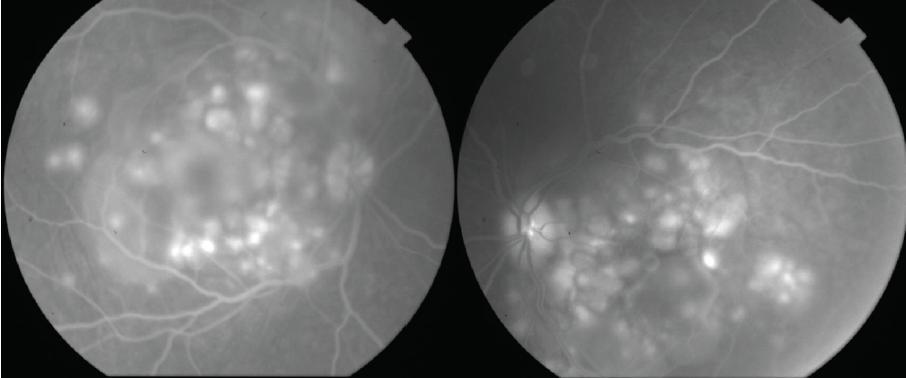

Dilated fundus examination revealed clear media without inflammation OU and numerous deep, discrete, and patchy yellow lesions throughout the posterior pole with irregular borders and multiple areas of distinct retinal elevation OU (Figure 1). The optic nerves were noted to be hyperemic OU without significant elevation, hemorrhage, or obscuration of vessels. Of note, there was no evidence of peripheral pathology or retinal vasculitis. OCT imaging showed numerous areas of intraretinal and subretinal fluid pockets of varying size with notable retinal and choroidal undulation through the macula (Figure 2). Fluorescein angiography showed multiple irregular patchy and pinpoint areas of hyperfluorescent foci throughout the posterior pole with leakage and distinct pockets of pooling in the later frames (Figure 3).

Figure 3. Fluorescein angiography shows multiple irregular areas of hyperfluorescent foci throughout the posterior pole with leakage and pooling in the later frames.